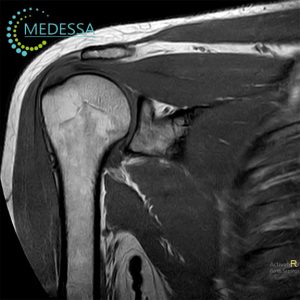

Магнітно-резонансна томографія (МРТ) суглобів та м’яких тканин — це високоточний метод медичної діагностики, який дозволяє детально візуалізувати анатомічні структури опорно-рухового апарату без використання іонізуючого випромінювання. Дослідження дає змогу оцінити стан колінного, плечового, тазостегнового, гомілковостопного, ліктьового, променево-зап’ясткового та інших суглобів, а також м’язів, сухожиль, зв’язок, менісків, фасцій та навколосуглобових тканин.

МРТ 3.0 Тесла в Одесі забезпечує максимальну деталізацію структур суглоба, що особливо важливо для раннього виявлення пошкоджень зв’язкового апарату, хрящової тканини та внутрішньосуглобових елементів. Високопольний томограф дозволяє діагностувати патології на ранніх стадіях, коли клінічні прояви можуть бути мінімальними.

Які структури візуалізує МРТ суглобів

- суглобовий хрящ;

- меніски;

- зв’язки;

- сухожилля;

- м’язи;

- синовіальна оболонка;

- суглобова капсула;

- кісткові структури;

- нерви;

- судини;

- бурси та фасції;

- навколосуглобові м’які тканини.